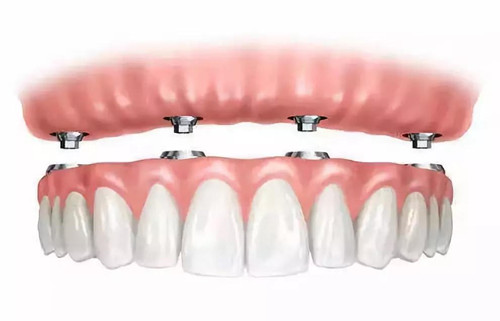

全颌固定种植义齿

种植固定义齿由于将义齿与种植体固定成一个整体,使得牙合力不易缓冲,易造成载荷过大,故采用此种修复方式应慎重,避免出现诸如种植体松动等并发症。

Reitz等研究认为带有前导的舌侧集中牙合是理想的牙合型设计。它不仅具有解剖牙合型的美观,又能减少侧向力,增加义齿的稳定性,故广泛使用。由于固定义齿无固位问题,故可根据对颌情况进行咬合设计。如对颌为活动义齿,则设计双侧平衡牙合;对颌是天然牙或固定义齿,则采用相互保护牙合,但有学者建议上下颌均为种植固定义齿时仍采用双侧平衡牙合。